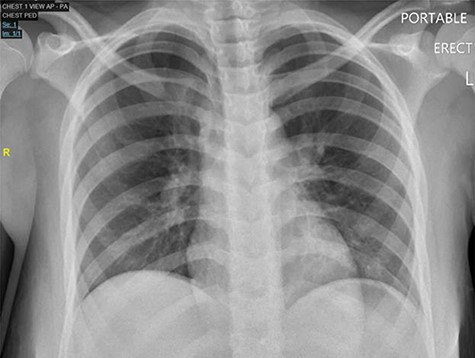

Case 2: A 13-year-old girl presented to the ED with a 3-day history of severe diffuse intermittent abdominal pain, worse in the periumbilical area, associated with nausea, vomiting and non-bloody diarrhea. No significant history was reported. On exam, the patient appeared sick, in acute distress, tachycardic and tachypneic with abdominal exam revealing diffuse tenderness with peritoneal signs. Laboratories showed normal WBC but lactic acidosis. Chest X-ray did not show free air under diaphragm (Fig. 3) and abdominal ultrasound showed moderate fluid in right upper quadrant of abdomen, for which CT of the abdomen and pelvis was ordered and it revealed free mesenteric fluid and extraluminal air in the pelvis suspicious for hollow viscus perforation (Fig. 4).

Chest X-ray PA, showing no cardiopulmonary disease, or free air under diaphragm.

Radiography is important in pediatric patients presenting acutely as they present with pneumoperitoneum [6], but studies have shown that X-ray may provide no radiological evidence of perforation as was seen in our case [WU4] [7]. CT reliably detected pneumoperitoneum in our cases. Thus, CT is valuable in the rapid diagnosis of PPU as it allows for prompt treatment and contributes to successful outcomes.